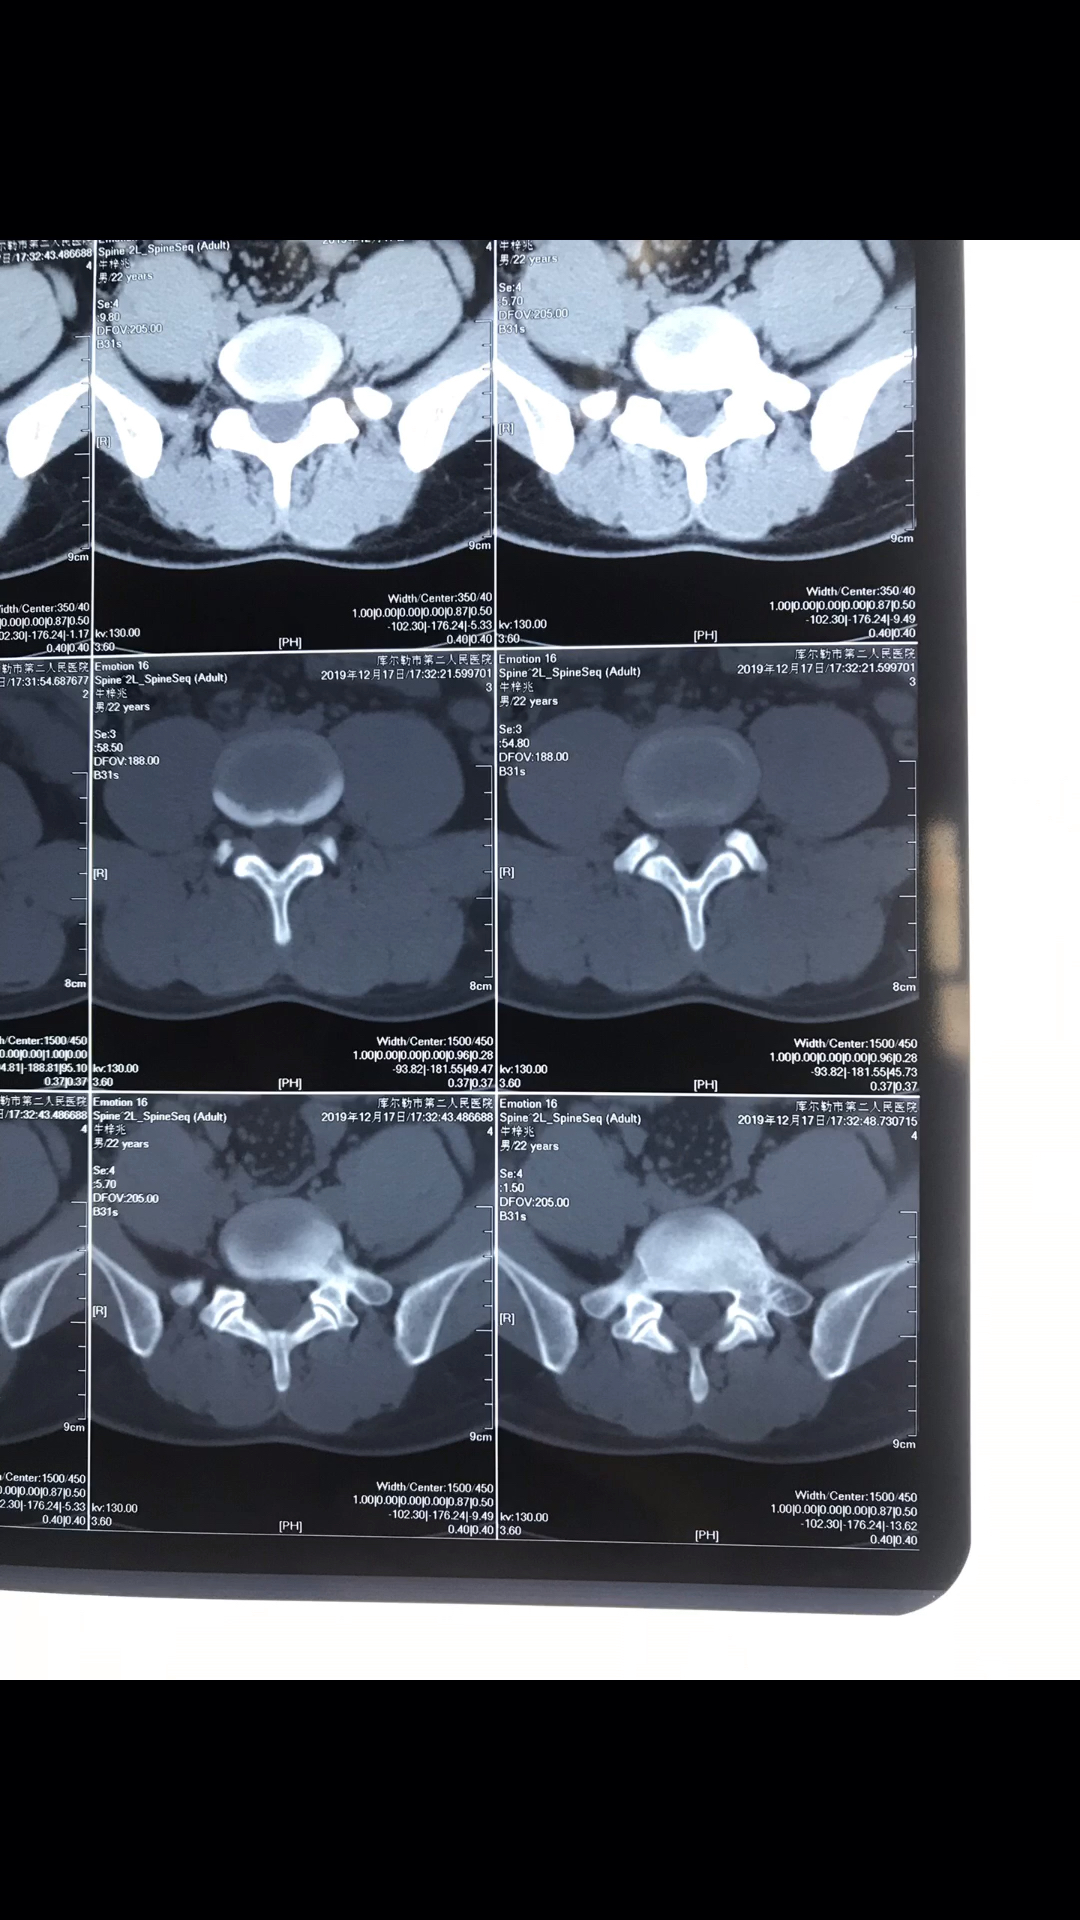

颈椎ct拍片,c4/5,c5/6椎间盘向后膨出,硬膜囊受压,哪位专家帮忙解释一

图片尺寸3264x2448